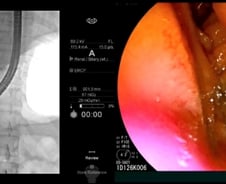

#. 26세 여성 이지은(가명) 씨는 지난달 기름진 음식을 먹고 명치가 심하게 쑤셔 병원 응급실을 찾았다. 복부CT(컴퓨터단층촬영) 등 검사를 받았지만 별다른 이상은 발견되지 않았고, 몇 시간 뒤 통증이 가라앉자 집으로 돌아갔다. 그러나 다음날 통증이 더 심해졌고 열과 함께 눈이 노랗게 변해 다시 응급실로 왔다. 담석증이 의심돼 초음파내시경 검사를 받은 결과, '담관결석(담석의 일종)'으로 진단받았다. 담석은 담즙이 뭉쳐져 돌처럼 단단하게 응고된 덩어리다. 담즙 성분의 비율이 변하면서 담석이 생기는 것으로 알려졌다. 담석은 주로 담즙을 보관하는 주머니(담낭)에서 생겨난 뒤, 담즙이 흐르는 담낭관·총담관으로 이동해 문제를 일으킨다. 총담관은 간내 담관·담낭에서 나오는 담낭관이 합류하는 관으로, 십이지장까지 연결된다. 담석이 있다고 무조건 증상이 나타나는 건 아니다. 담석을 가진 환자의 80%는 특별한 문제 없이 생활한다. 하지만 20%는 담석이 담낭관이나 총담관을 막아 통증을 유발하거